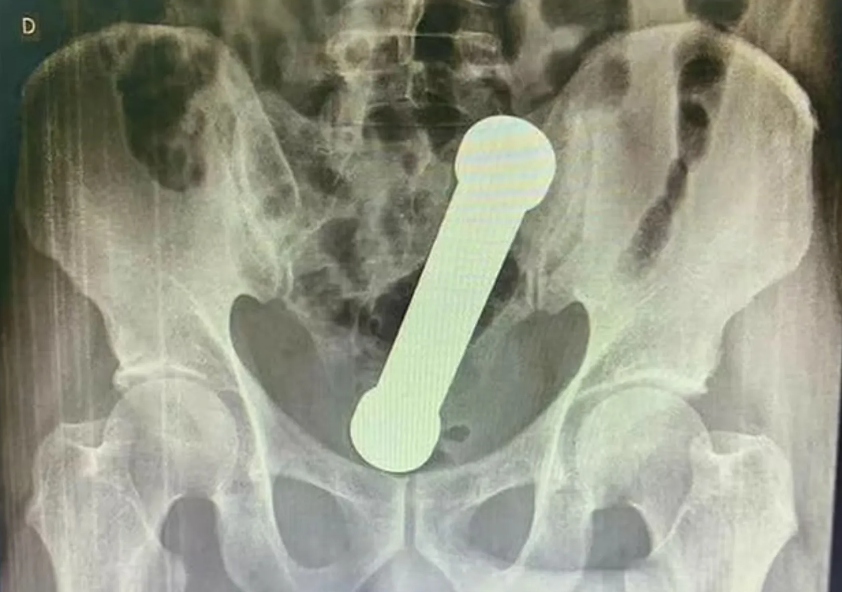

رجل خمسيني اشتكى من ألـ،،ـم في البطن وعندما ذهب للطوارئ تفاجأ الأطباء بما وجدوا!!